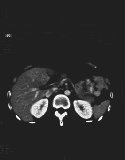

X線CT